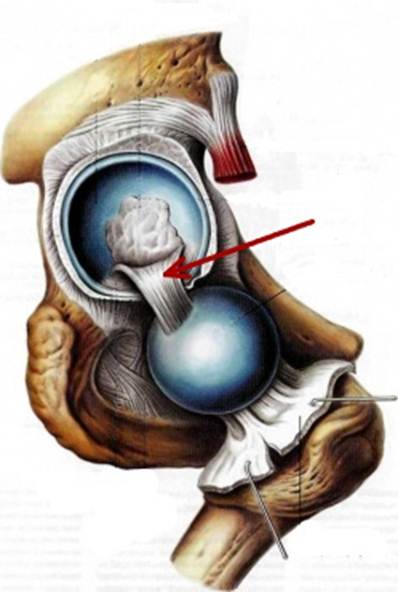

S: На рисунке обозначен art. Coxae (латинский язык).

S: Стрелка указывает на zona orbicularis

S: Стрелка указывает на lig. Ischiofemorale

S: Стрелки указывают на lig. iliofemorale

S: Стрелка указывает на lig. pubofemorale

S: Стрелка указывает на labrum acetabuli

S: Стрелка указывает на lig. Capitis femoris

S: Стрелка указывает на facies lunata